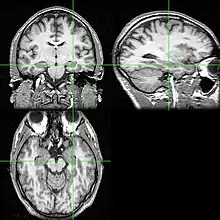

Imbalances found in certain serotonin receptor activity in cortical association regions, including the frontal lobes, are found in individuals with AN and may be the cause of impairment in their working memory, attention, motivation, and concentration.[31][32] In addition, the ability of individuals with AN to activate remote memories, learn new information, plan ahead, regulate actions according to environmental stimuli, and shift behavioural sets appropriately are all implicated.[31] Some individuals with anorexia nervosa (AN) have an inability to change their pattern response behaviours, which has been linked to disturbances found in the cortical and subgenual cingulate - mesial temporal pathways of these individuals.[31]

The reduced blood flow in the limbic system of individuals with AN is what mostly accounts for their impairment in cognitive functioning.[33] More specifically, the set of structures in the limbic system including the temporal lobes and adjacent structures like the hypothalamus, amygdala, and hippocampus are important in memory as well as emotion, appetite regulation, motivation, and perception, and are therefore implicated.[33] Reduced cerebral blood flow to these areas have also been associated with impairments in complex visual memory, enhanced information processing and visuospatial ability.[34]

Individuals with AN have been reported to have prolonged exposure to high levels of corticosteroids, a class of chemicals involved in things such as stress and behaviour,[35] and prolonged exposure to corticosteroids has been associated with impairments in memory and learning.[35][36][37][38][39] The hippocampus is an area of the brain that is dense with corticosteroid receptors, and therefore may be what is mediating these impairments.[36][37][38][39][40][41][42]

Activation of the medial prefrontal cortex has been shown in some studies to reflect self-schemata evaluation of relevant information, and could be used to investigate body image representations in individuals with bulimia nervosa (BN).[43] In addition, increased activation in brain areas associated with information processing like the dorsal and anterior medial prefrontal cortex (mPFC), adjacent areas of the cingulate cortex, and the posterior cingulate and precuneus have been implicated in individuals with BN,[43] meaning that the working memory used to actively manipulate information in these individuals is affected.

Areas of the brain such as the insula[44] and anterior circulate cortex (ACC) have been found to be disturbed in individuals with BN.[45] These areas are involved in self-regulation as well as executive control which controls cognitive processes including working memory, and may be the reason for impairment.[46]

An increase in dopamine in the caudate and putamen have been found in binge eaters,[47] and studies have found a decrease in a particular serotonin transporter (5-HT) in binge eaters compared to controls.[48] Both the caudate nucleus and putamen make up the dorsal striatum and are important as part of the brain's memory system. Dopamine is required to allow these structures to perform properly and thus this is affected in individuals with binge eating disorders, however the exact mechanism is unknown.

A dysregulation of the ventral limbic circuit has been found in individuals who binge eat.[46] The ventral limbic circuit is important in the regulation of feeding behaviour and includes the amygdalae, insula, ventral striatum, ventral regions of the anterior ACC, and orbitofrontal cortex (OFC).[46] A stronger activation of the OFC has been found in patients who binge eat compared to normal weight controls, when viewing pictures of food.[44][49]